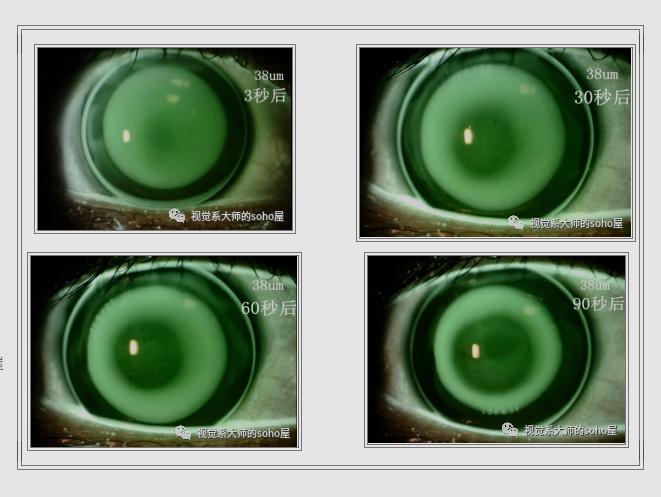

我从视频中截取了戴后3秒、30秒、60秒和90秒的图片(图中38um是理论计算的顶间隙apical clearance)。

从图中可以发现,随着时间推迟,荧光素在镜下有明显的分布改变。3秒时明显的配适偏紧(矢高过高),到30秒中央出现2~3mm暗区,60秒暗区继续扩大接近于可接受的荧光配适,到90秒时bc区5~6mm,已完全看不出矢高过高的迹象。图像变化那么大,我们不禁有了疑问: